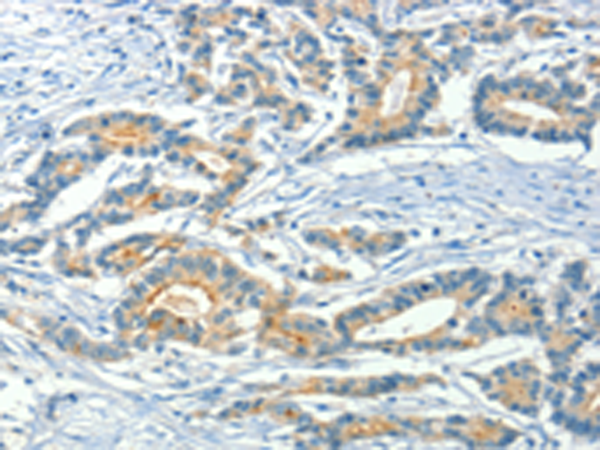

分类: 科研抗体货号: P08003别名: NIP3应用: WB,IHC反应种属: Human, Mouse